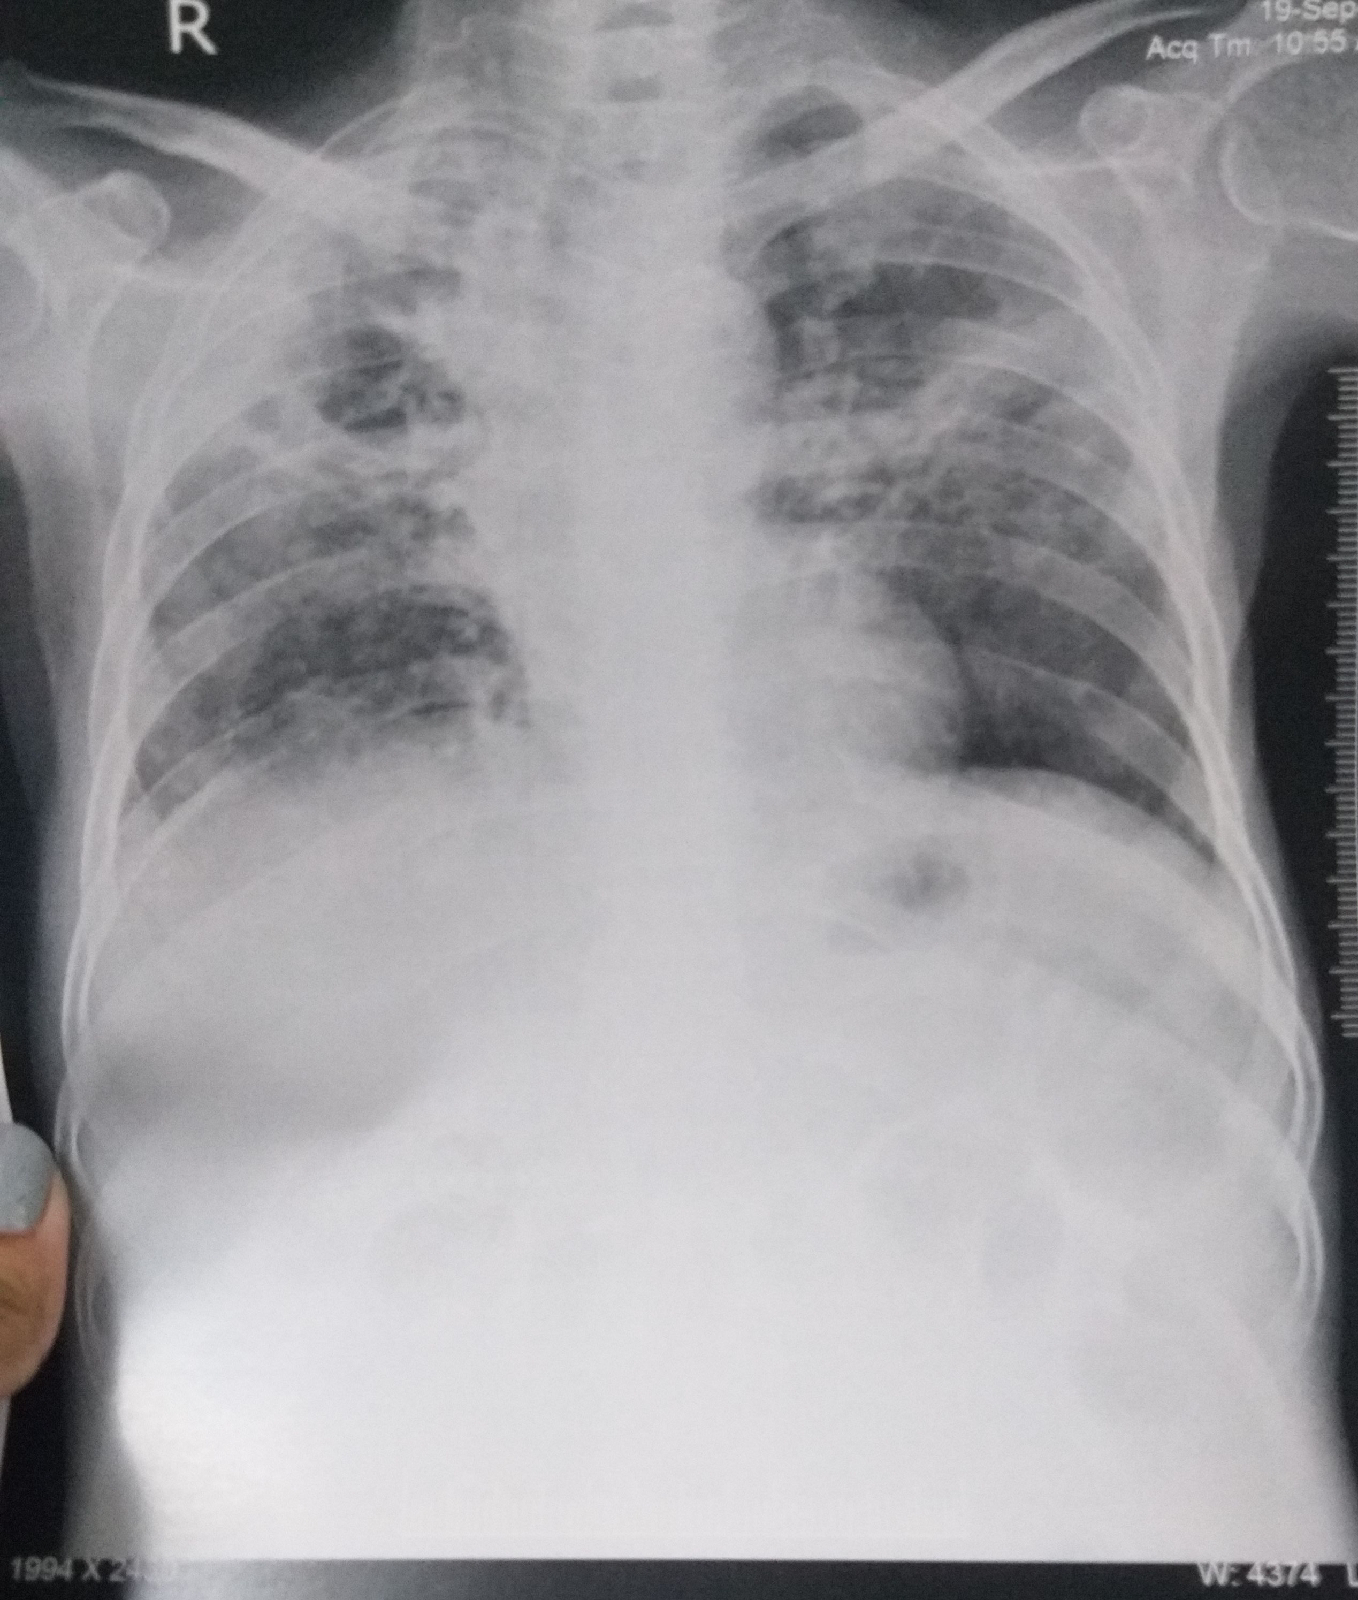

In july 2020, he started having fever - low grade which relieves on taking medication (on and off) more during nights,not associated with chills, rigors and sweating.It is associated with dry cough- more at night,insidious in onset,progressive in nature,more on lying down position.he was also complaining of Generalised weakness from july, most of the time, confined to bed.On july 18th,he had dog bite to his right knee(had vaccination 4 doses).For these symptoms,he got COVID Ag test done in july,turned out to be negative.In september,he started having abdominal tightness(after taking spicy foods ),pedal edema - pitting type (on and off) shortness of breath, all symptoms from 1 month  for which he was referred to govt hospital where he was diagnosed as sputum positive TB and started ATT -  3 tablets at once after break fast(now,it is his 4th day using them).H/o loose stools from 20 days watery in consistency,non foul smelling, no mucus,2 to 3 episodes per day.not associated with pain abdomen , vomitings.

Inspiratory  Crepts Present in right and left mammary,infra mammary,left axillary and infra axillary areas,bronchial breath sounds heard in right infra mammary area.

Diagnosis - pulmonary koch's with chronic liver disease with chronic pancreatitis with type 2 DM with hyponatremia secondary to SIADH (pulmonary koch's) with gross ascites(transudative).